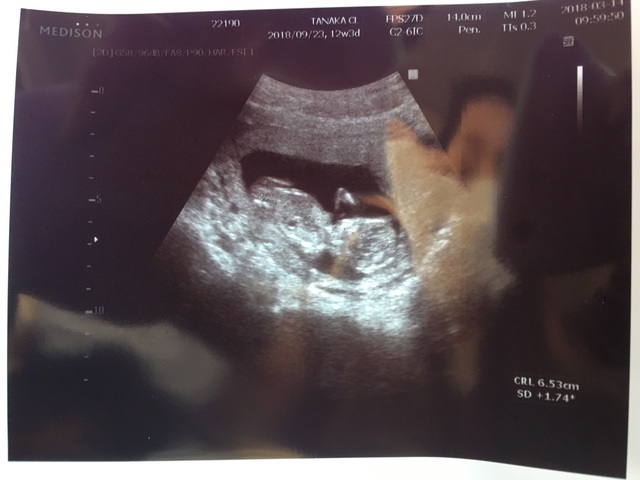

12週0日(12w0d・性別不明)|どどどこ さん(26歳)

エコー写真撮影時のエピソード:

体の上のやつは、赤ちゃんの手です。 手をこっちに向けて振ってくれてるみたいで、とてもお気に入りです!

上の子もこれを見て、手を振り返していました! とても微笑ましい姿で 産まれてくるのが楽しみです!